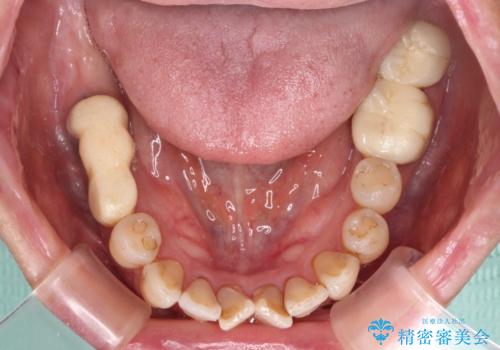

- 治療をおこなって以来、クラウン周りの歯肉から出血が続くとのことで来院された患者様です。

診察を行ったところ、クラウンと歯の境目が不適合で汚れが溜まりやすく、炎症を起こしている状態でした。

治療を終えたばかりですが、出血を改善するためには作り直しが必要と判断し、オールセラミッククラウンにて補綴治療することとしました。